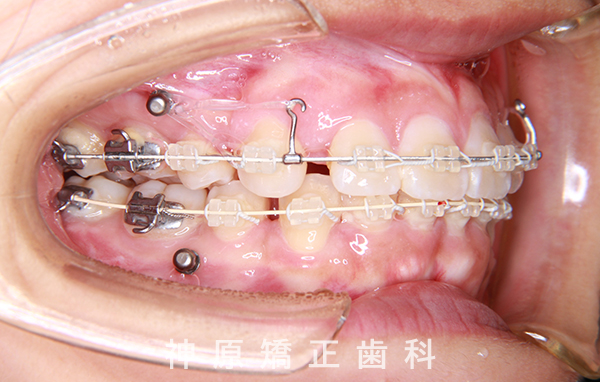

マルチブラケット装着1年後

口元の突出感と下の歯並びの乱れを改善するため、小臼歯を抜歯することにしました。抜いたスペースを利用して、前歯をできるだけ後ろに移動させるため、上下に歯科矯正用アンカースクリューを使用する計画を立てました。治療の目標について同意を得た後、矯正治療を開始しました。歯の動きが順調で、1年9カ月で治療が完了しました。その結果、側貌はE-lineに調和したバランスの良い仕上がりになりました。